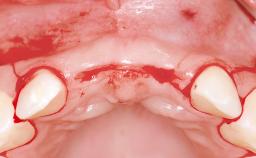

Replacement of Teeth 12 and 13 with Tissue-Level Implants

In 2001, a 48-year-old woman presented at a dental clinic with a failing fixed partial denture spanning from teeth 13 to 21. She was experiencing pain upon function, tenderness to palpation facial to tooth 13, and severe mobility of the prosthesis. Radiographic and clinical assessment revealed a subcrestal fracture of tooth 13, making its restoration unlikely. It was determined by the clinician that the tooth needed to be extracted prior to proceeding any further with dental care. After the extraction, the patient lost confidence in the progression of her treatment and sought consultation at the Center for Implant Dentistry. At her consultation visit in our clinic, an extra- and intraoral clinical examination revealed a medium lip line at full smile and an edentulous area spanning from 13 to 12 with both vertical and horizontal deficits in hard and soft tissue.

Bone Augmentation Horizontal|Staged|Vertical

Augmentation Materials Autogenous chips|Autogenous block(s)|Membrane

Soft Tissue Anatomy Intact Defective

Bone Volume Deficient vertically or deficient vertically AND horizontally